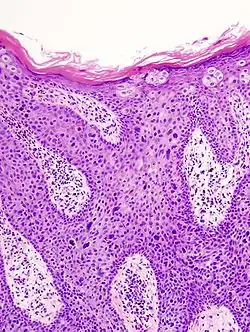

In situ disease

Bowen's disease is essentially equivalent to and used interchangeably with cSCC in situ, when not having invaded through the basement membrane.[12] Depending on source, it is classified as precancerous[13] or cSCC in situ (technically cancerous but non-invasive).[48][49] In cSCC in situ (Bowen's disease), atypical squamous cells proliferate through the whole thickness of the epidermis.[12] The entire tumor is confined to the epidermis and does not invade into the dermis.[12] The cells are often highly atypical under the microscope, and may look more unusual than the cells of some invasive squamous-cell carcinomas.[12]

cSCC in situ -

cSCC in situ